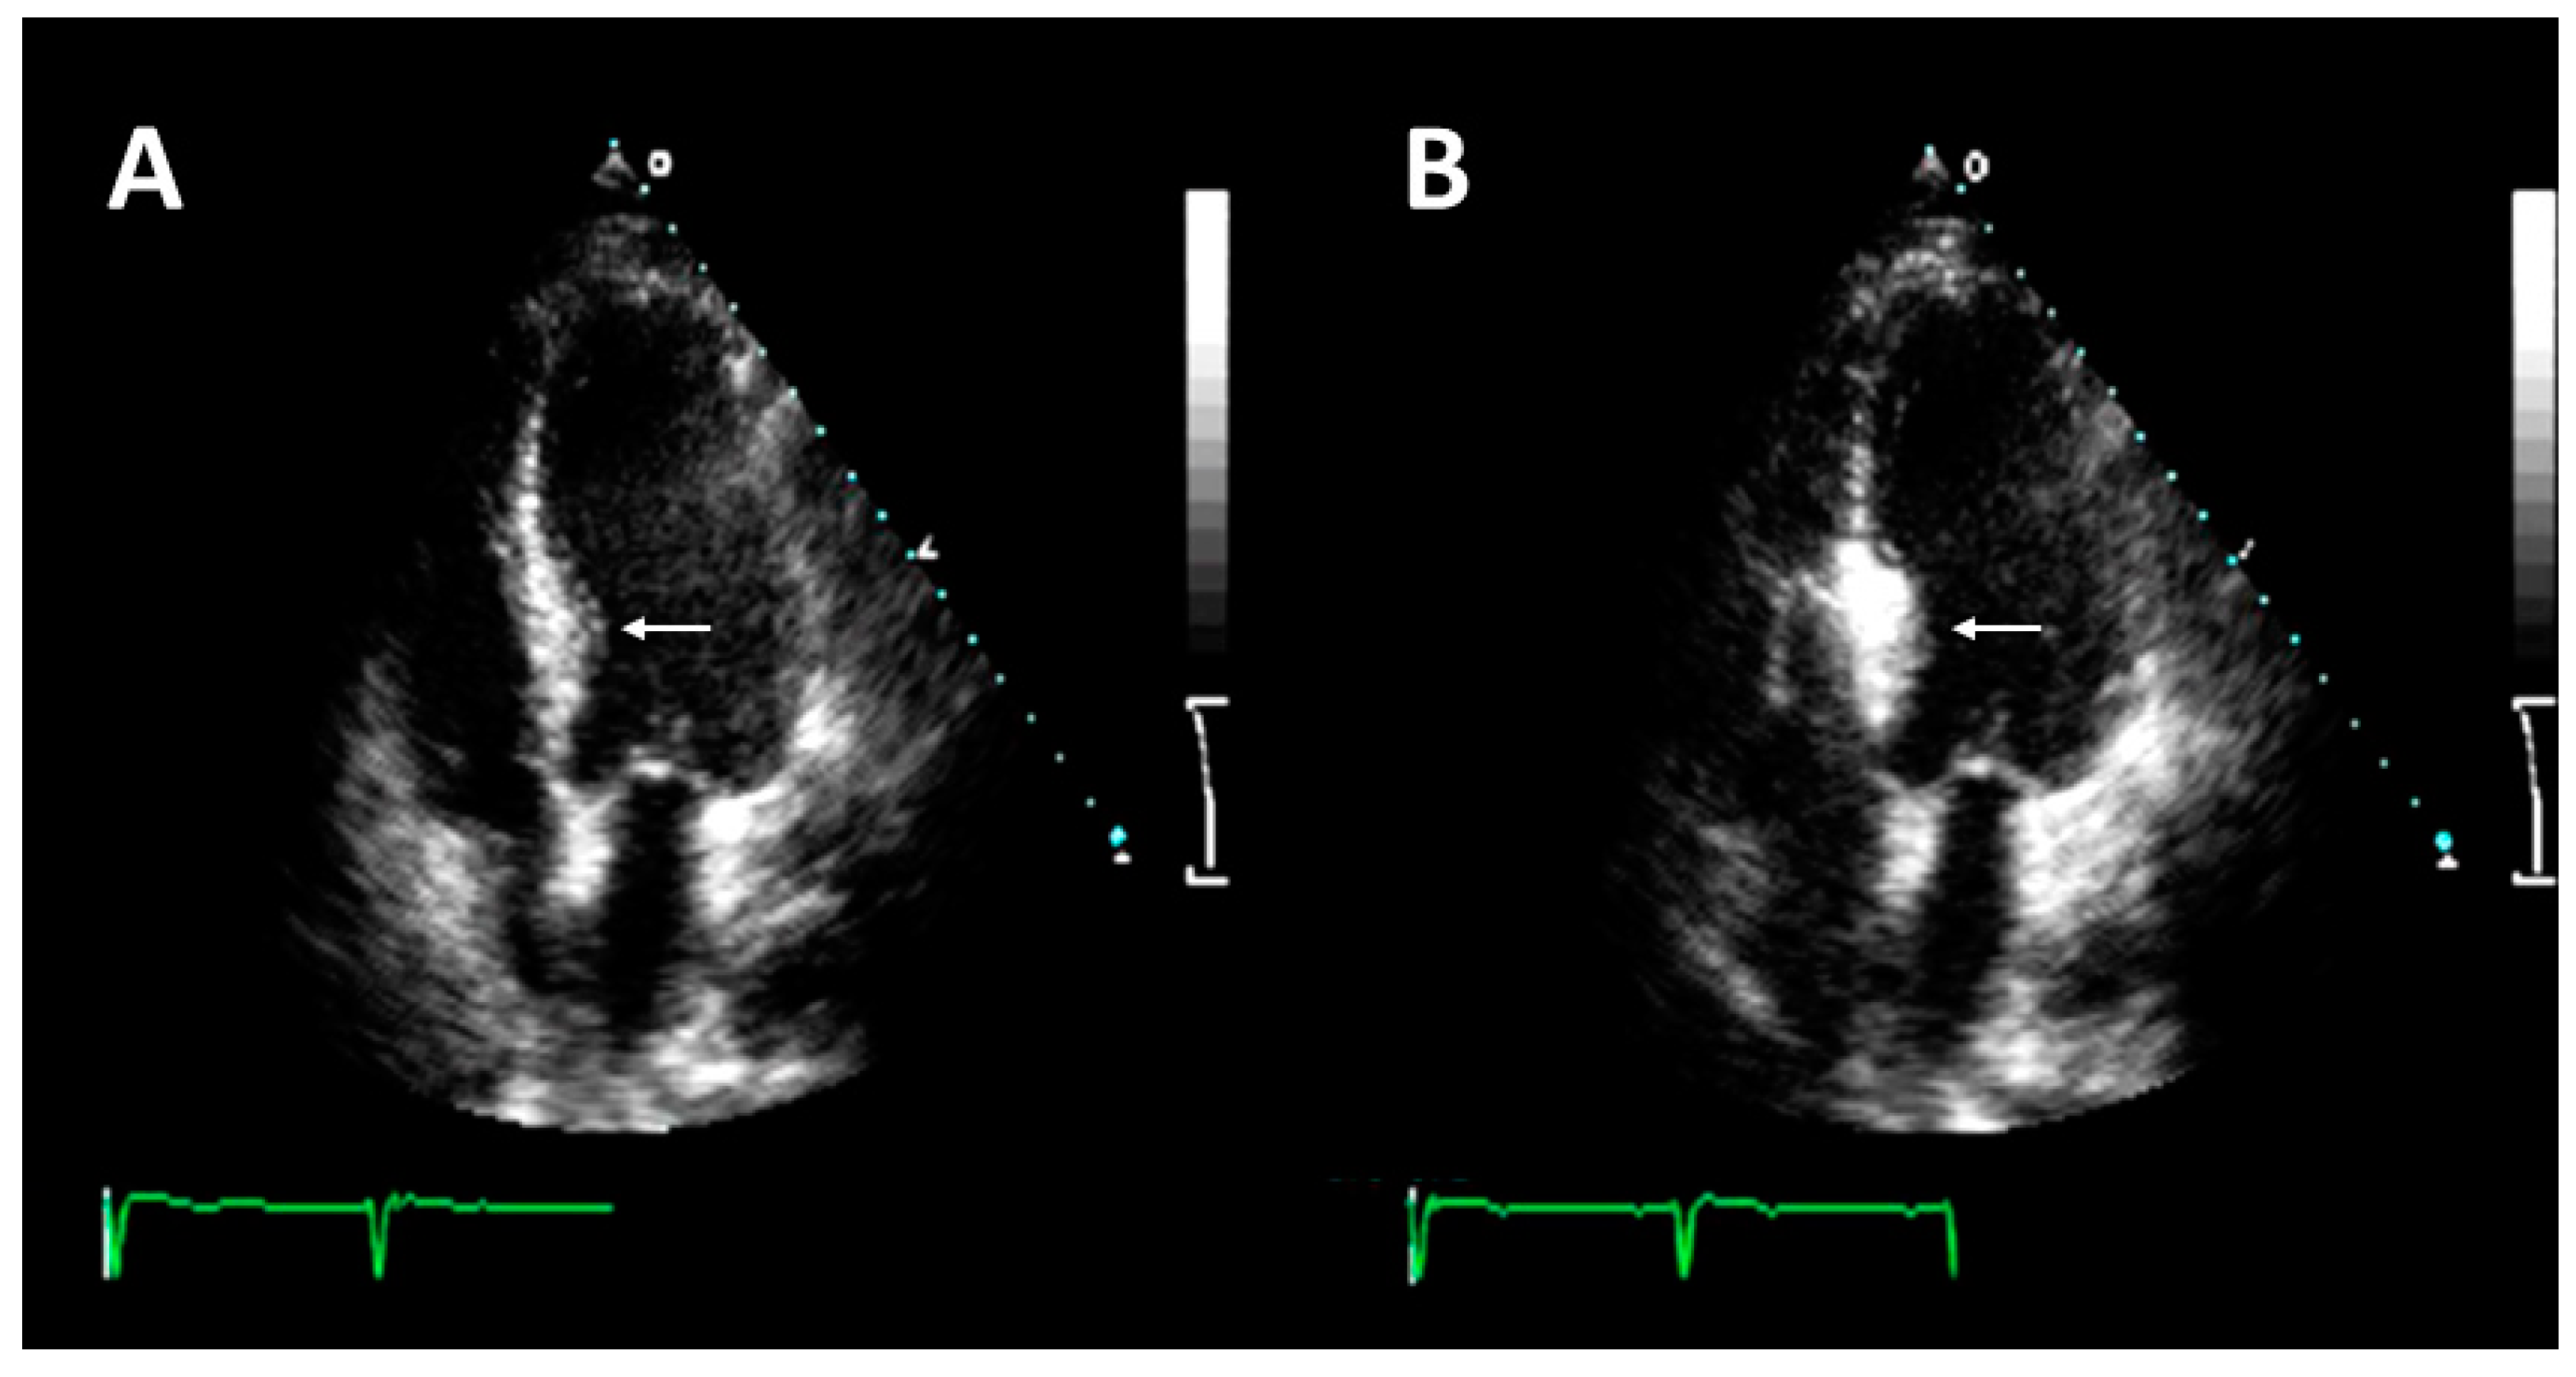

3.3. Description of the Procedure

- Pelliccia, F.; Niccoli, G.; Gragnano, F.; Limongelli, G.; Moscarella, E.; Andò, G.; Esposito, A.; Stabile, E.; Ussia, G.P.; Tarantini, G.; et al. Alcohol septal ablation for hypertrophic obstructive cardiomyopathy: A contemporary reappraisal. EuroIntervention 2019, 15, 411–417. [Google Scholar] [CrossRef]

- Faber, L.; Seggewiss, H.; Ziemssen, P.; Gleichmann, U. Intraprocedural myocardial contrast echocardiography as a routine procedure in percutaneous transluminal septal myocardial ablation: Detection of threatening myocardial necrosis distant from the septal target area. Catheter. Cardiovasc. Interv. 1999, 47, 462–466. [Google Scholar] [CrossRef]

- Moya Mur, J.L.; Salido Tahoces, L.; Mestre Barceló, J.L.; Rodríguez Muñoz, D.; Hernández, R.; Fernández-Golfín, C.; Zamorano Gómez, J.L. Alcohol septal ablation in hypertrophic cardiomyopathy. 3D contrast echocardiography allows localization and quantification of the extension of intraprocedural vascular recruitment. Int. J. Cardiol. 2014, 174, 761–762. [Google Scholar] [CrossRef]